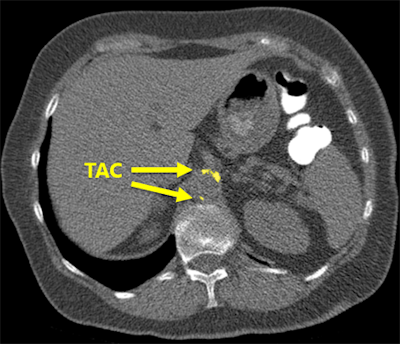

The software correctly detected an example of thoracic aortic calcification near the base of the lungs."We found that the system struggles with extreme cases, but overall performs very well," he said. "This can potentially enable fully automatic assessment of cardiovascular risk in all patients who receive a chest CT scan for whatever indication."